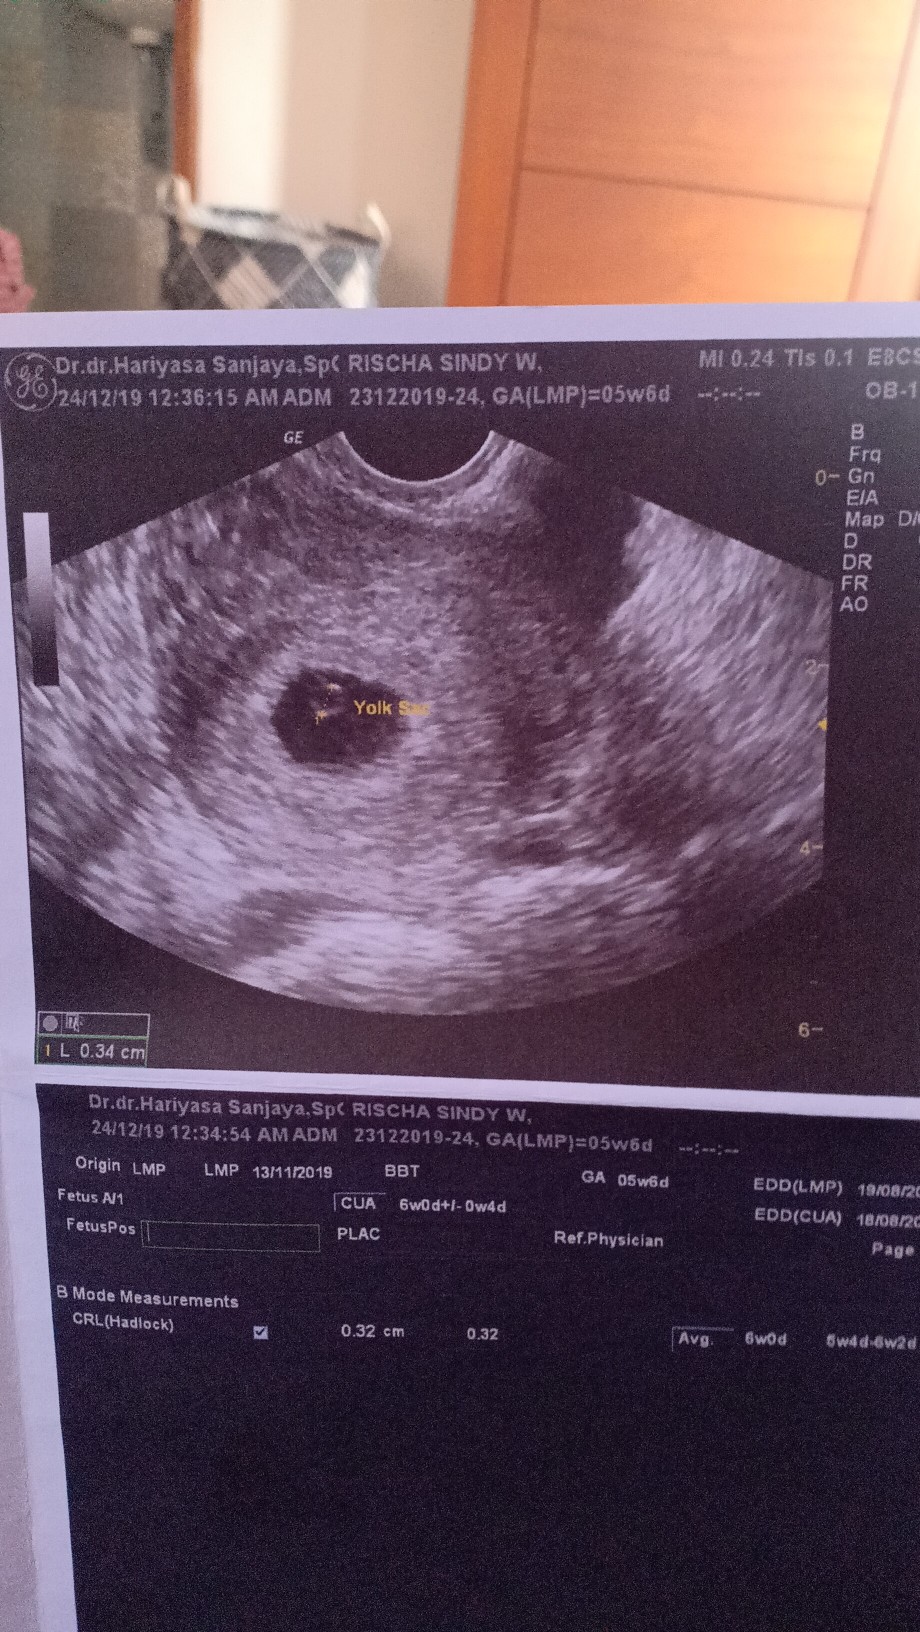

Ini usg pertama kalii, dokter lsg kasii selamaat.. Alhamdulillah positif, kliatan kantung rahim sama yolk sac nyab